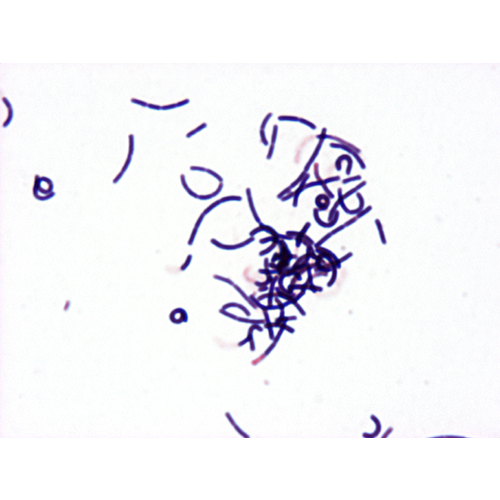

Bacillus Subtilis

This is typical of Bacillus spp. with large Gram positive rods. Note the size reference in the upper right hand corner with E. coli and Enterococcus Faecalis.